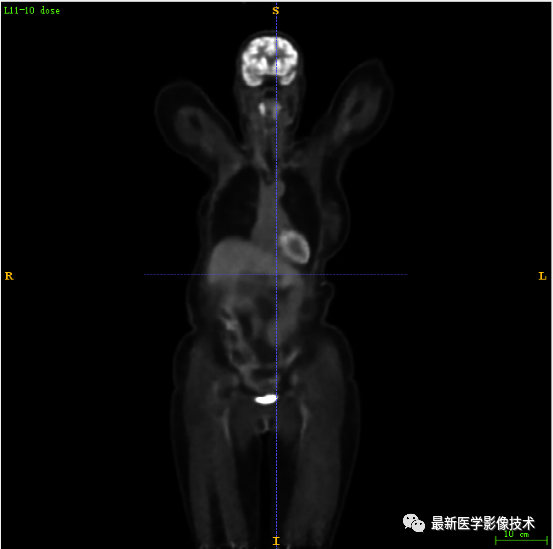

7.4、低剂量20重建结果

第一张是低剂量20的PET图像,第二张是full剂量PET图像,第三张是网络重建的PET图像。